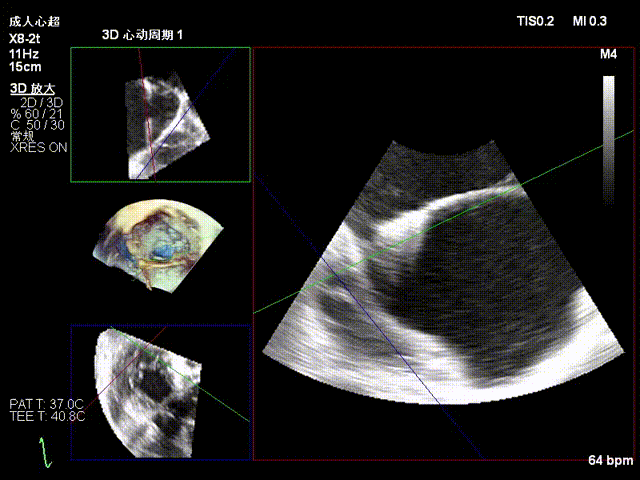

2.Annuloplasty Effect: Annular morphology remodeled, central gap significantly reduced.

Preoperative 3D

Postoperative 3D